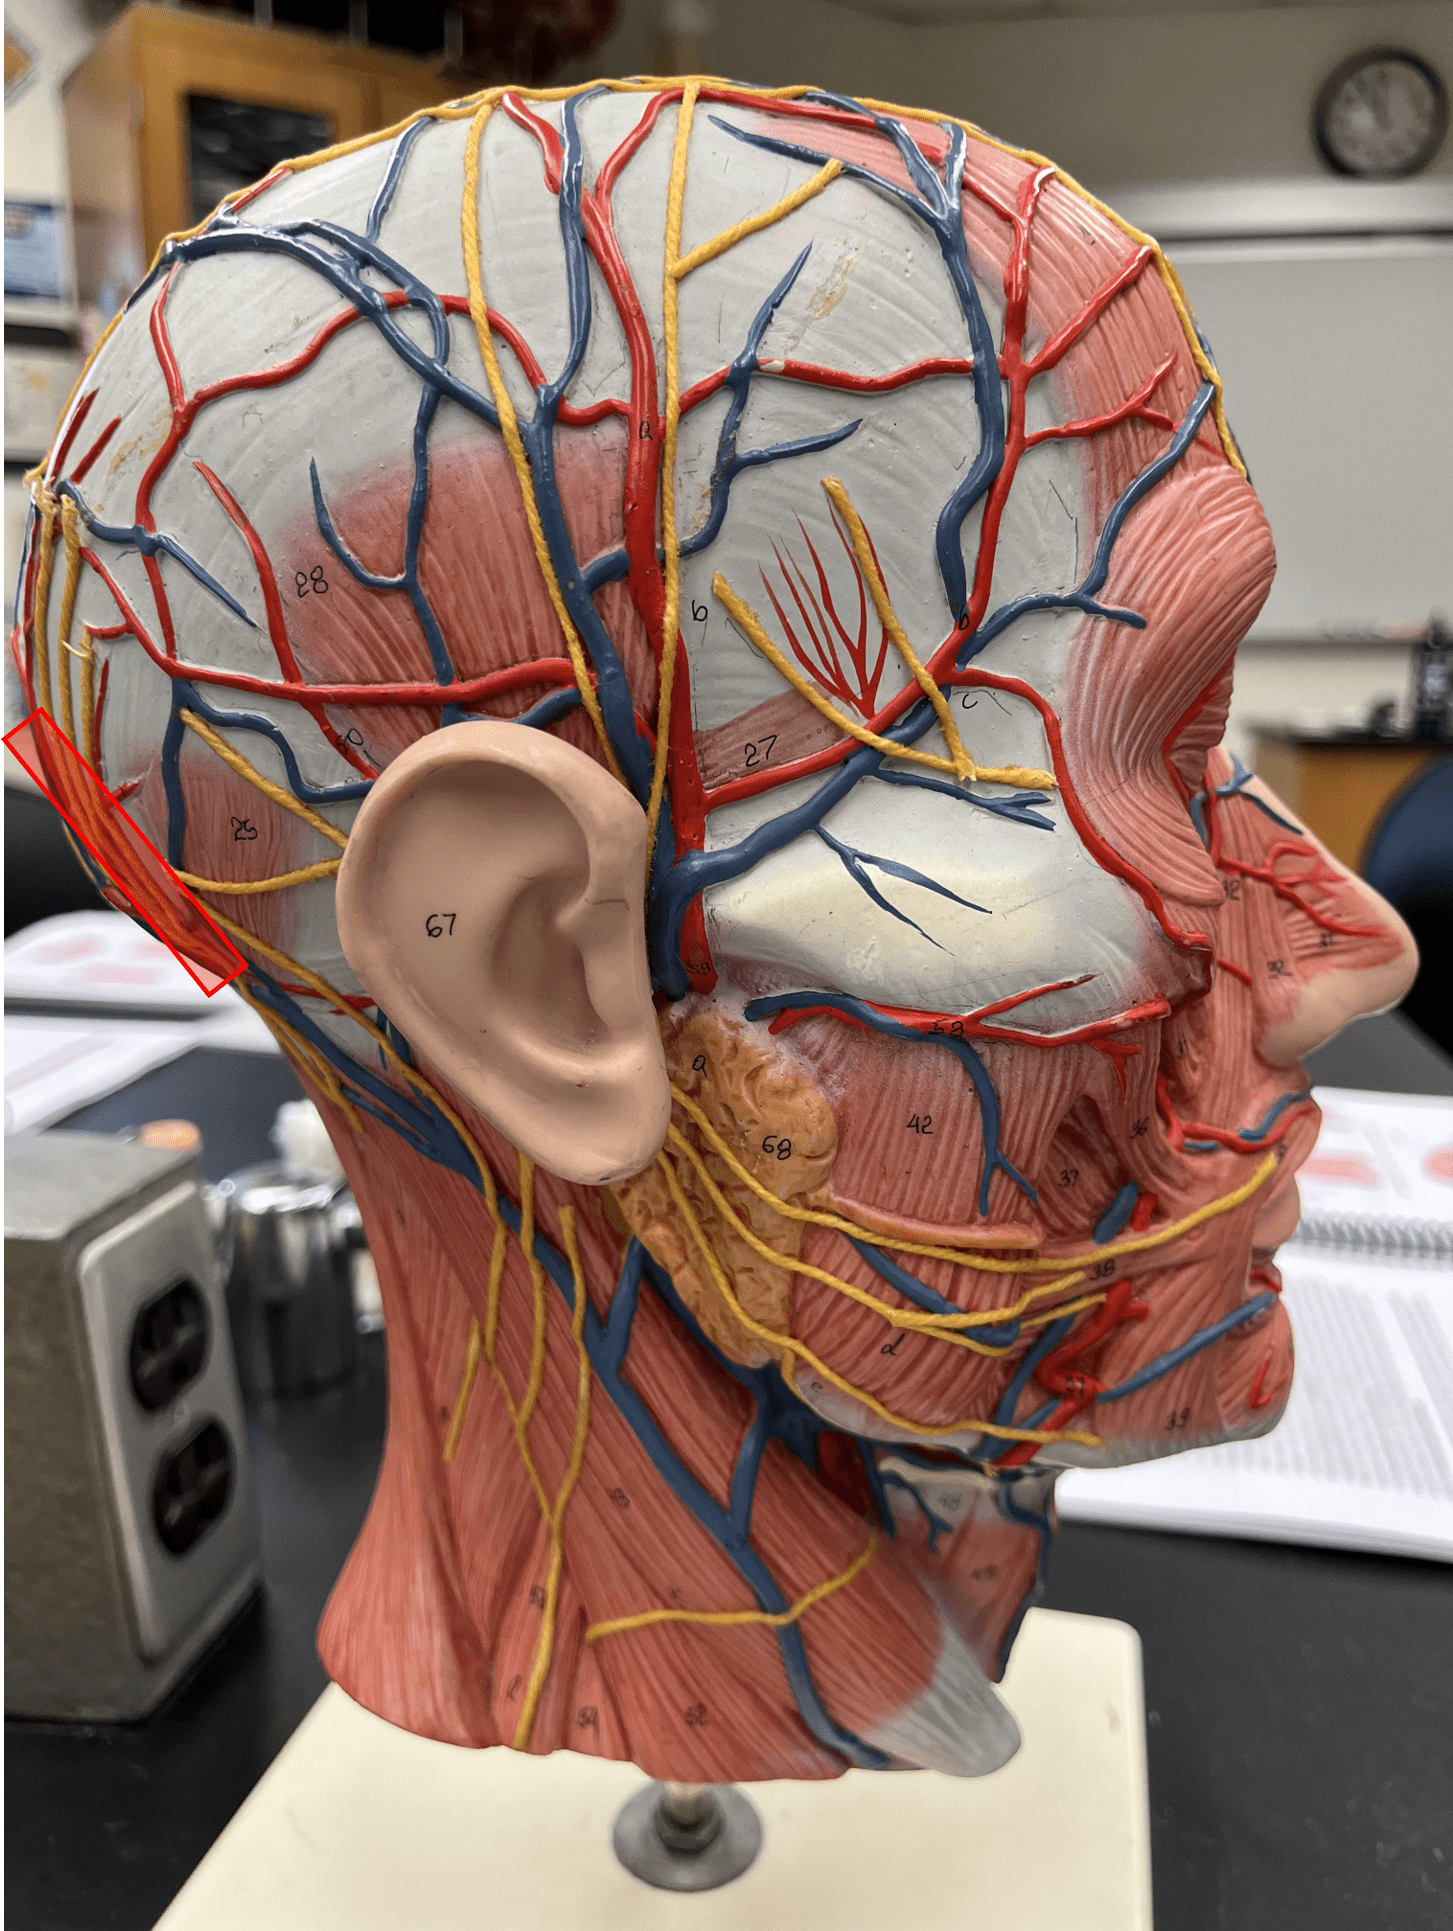

occipital artery

• An artery of the head and neck.

• Originates from the external carotid artery.

• Supplies the posterior scalp.

• Originates from the external carotid artery.

• Supplies the posterior scalp.